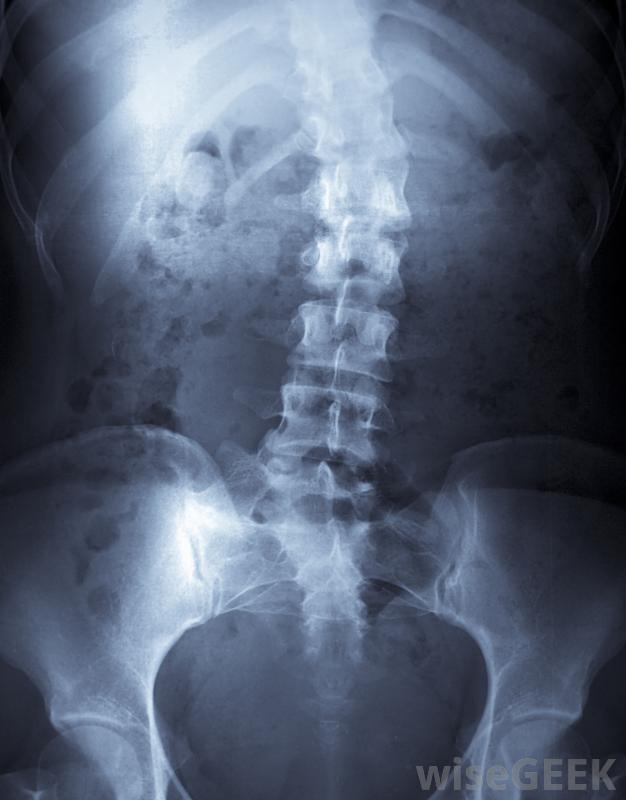

胸廓成形術包括縮短胸部特定部位的肋骨。對于脊柱側凸患者來說,這是一種相當常見的手術,因為它可以使脊柱側凸引起的肋骨隆起變小,也不那么嚴重。通常,病人在完成脊柱側凸矯正手術后,將進行胸腔成形術。胸廓成形術也可用于...

令人驚訝的是,在胸腔成形術完成后的兩到四個月內,肋骨或肋骨會重新長出并形成一個或多個新的肋骨。一旦愈合過程完成,新的肋骨將和之前的肋骨一樣堅固。不幸的是,如果脊柱的彎曲繼續下去因此,對脊柱側凸的治療以及肋骨隆起的切除是非常重要的。